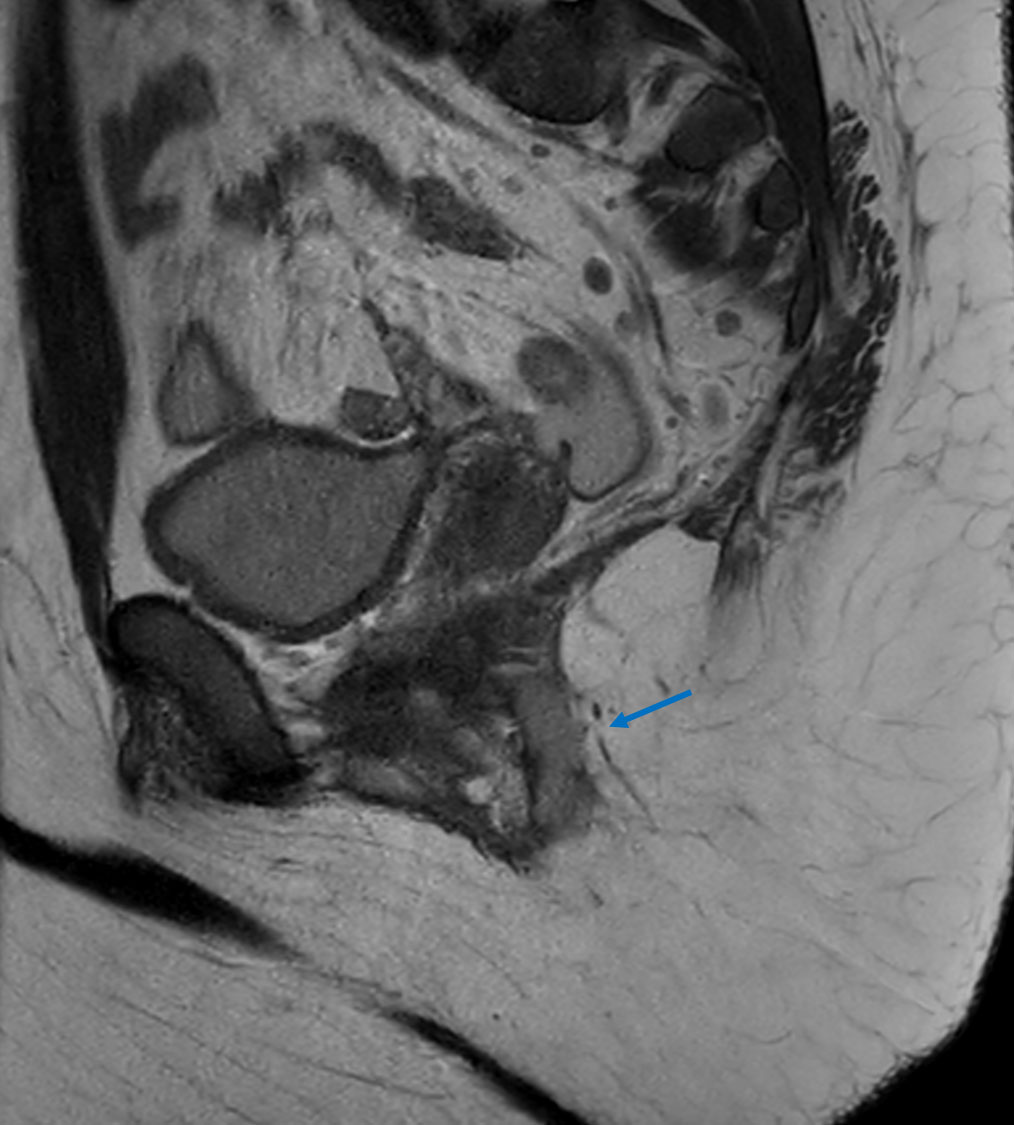

Sagittal T2w TSE